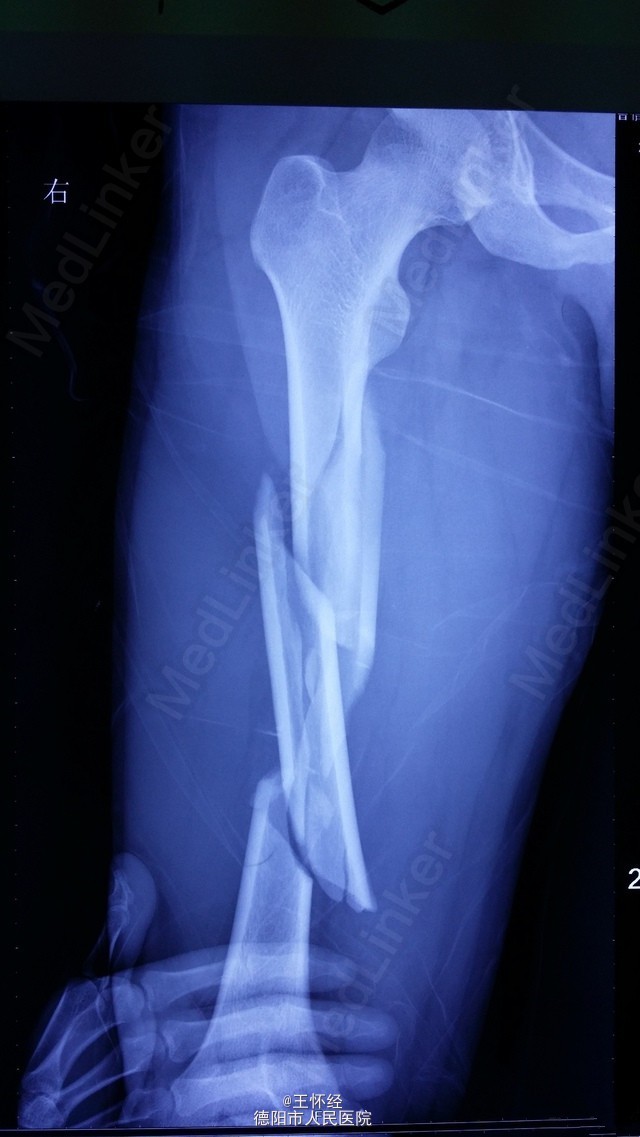

右股骨干粉碎性骨折一例

患者男性,26岁,重物砸伤右大腿后畸形1天,外院转入;予闭合复位髓内钉固定,由于为长节段骨折,骨折距离股骨髁较近,固定不够稳定,术后有骨不连、内固定失效的风险,故加上阻挡钉可以增加骨折固定的稳定性。